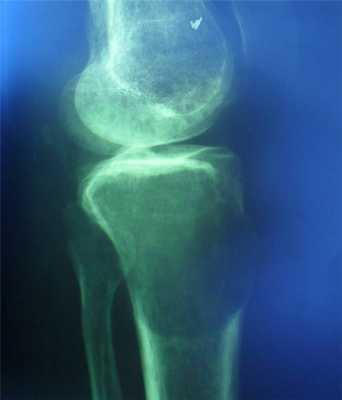

Все больные были разделены на группы в зависимости от размера очагового образования: 1-ю группу (диаметр ООЛ 0,5-1; рис. 1) составили 9 мужчин и 14 женщин, 2-ю группу (диаметр ООЛ 1-2 см; рис. 2) - 30 мужчин и 13 женщин, 3-ю группу (множественные ООЛ; рис. 3) - 27 мужчин и 17 женщин.

Рис. 2. Компьютерная томограмма груди пациента 2-й группы.

Больные 1-й группыбыли оперированы из миниторакотомного доступа, 2-й - из миниторакотомного доступа с видеоподдержкой, 3-й - из видеоторакоскопического доступа. Результаты гистологического исследования удаленных патологических образований представлены в таблице.

Во 2-й группе у 13 пациентов был выявлен рак легкого. Доброкачественные опухоли (гамартомы) легкого имелись у 18 больных, у 7 пациентов была диагностирована туберкулома. Таким образом, в этой группе частота злокачественных и доброкачественных опухолей вместе с туберкуломами составила 88,4%.